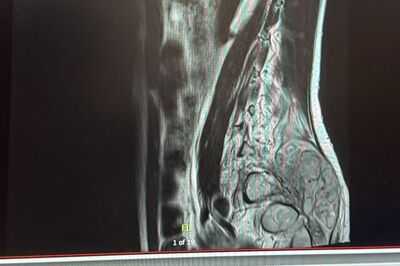

Further tests back home in the UK, involving multiple scans and examinations including an MRI, were carried out privately but didn’t find the cause, only a suspected herniated disc. Further medication was given to Leah to help manage the pain. An osteopath then told Leah she had a damaged tailbone.

An ultrasound did not find the source of her pain. Leah also claims she was refused other scans. Her boyfriend, who grew up in Greece, booked a short trip to take her there to have MRIs and an X-ray, which found abnormalities. Leah was then referred for a biopsy with the NHS.

Leah was finally diagnosed with Ewing sarcoma in December 2023, a form of cancer. Her diagnosis came around two years after her symptoms began towards the end of 2021.